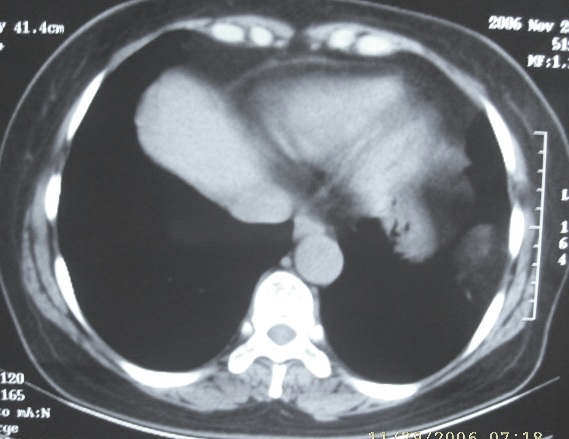

ct值-106

图象质量差,ct图片太少没有临床资料.猜出结果太伟大了

你用黑白模式拍啊.看不清,哪的ct值,密度都一样吗?脂肪瘤?

图像处理了一下,还是不很好!我觉得应该是脂肪瘤或者腹腔脂肪组织

ct图片少又差,还不如就胸片让人来猜,左胸腔包裹性积液.

脂肪组织   或膈疝

有可能是大网膜疝,往下扫两层看看.

ct图片少难度太大,我考虑1、左侧包裹性胸腔积液  2、炎性假瘤

考虑错构瘤

ct图片少难度太大,考虑1、左侧包裹性胸腔积液  2、炎性假瘤

图片少、质量不佳,难度大,考虑错构瘤。